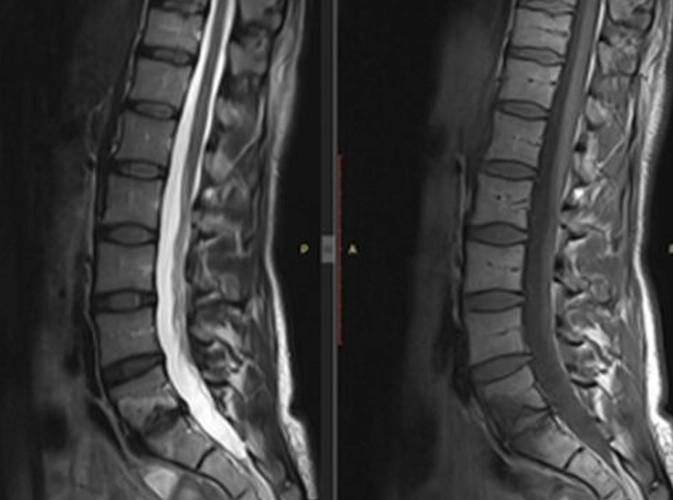

İncelemeler: Laboratuvar: AFR normal. Rutin biyokimya normal. Brucella negatif. HLA-B27 negatif. Görüntüleme: Sakroiliyak MR olağan. Mevcut lomber MR’da L5–S1 düzeyinde spondilodiskit açısından şüpheli görünüm izlenmesi üzerine kontrastlı lomber MR istendi.

Kemik sintigrafisi görüldükten sonra spondilodiskit olasılığı elendi. L5-S1'deki disk lezyonu geçirilmiş bir travma ya da Schmorl nodülüne sekonder olarak artmış yoğun dejeneratif değişiklikler olarak değerlendirildi. 1600 mg/gün NSAİİ tedavisi ile kısmi fayda görüldü. Ağrı sadece sol değil sağ kasık bölgesine de ara ara yayılım gösteriyor artık ancak şiddet daha azdı. Hastaya fizyoterapi, günlük yaşam aktivitelerinde dikkat etmesi gerekenler ve kısıtlamalar önerildi ve takip planlandı.